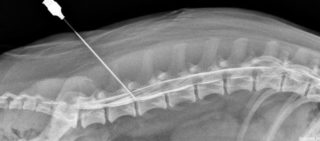

Кеторол в уколах назначают для купирования острой боли, а не для лечения хронического болевого синдрома. Максимальный эффект наблюдается через час после инъекции, длительность действия составляет около пяти часов. Рекомендуется вводить 10-30 мг однократно или каждые 4-6 часов. Суточная доза для взрослых до 65 лет не должна превышать 30 мг. Обычно препарат назначают на 5 дней, вводить нужно глубоко, для чего требуются длинные иглы.

Уколы Кеторол вводятся внутримышечно, реже — внутривенно. Обычно раствор вводят в наружную верхнюю треть бедра, плечо или ягодицу. Инъекцию следует делать глубоко в мышцу и медленно.